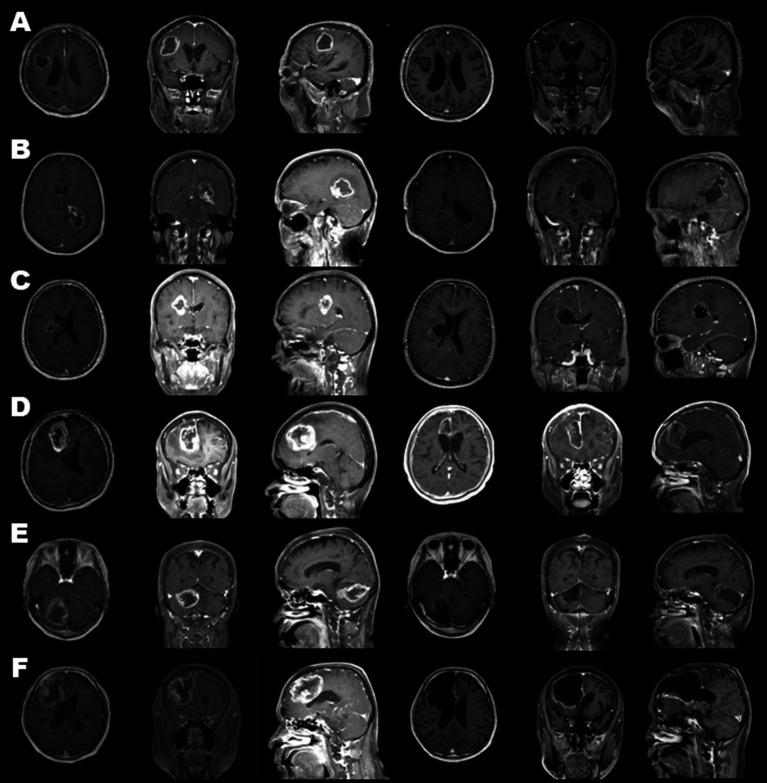

Medical records of six consecutive glioblastoma patients who received exclusive endoscopic removal between September and November 2020 were analyzed. Preoperative tumor embolization was performed in cases with marked tumor stain and proper feeder arteries having an abnormal shape, for instance, tortuous or dilated, without passing through branches to the normal brain. Endoscopic tumor removal through a key-hole craniotomy was performed by using an inside-out excision for a deep-seated lesion, with the addition of an outside-in extirpation for a shallow portion when needed.

Endoscopic removal was successfully performed in all six cases. Before resection, endovascular tumor embolization was performed in four cases with no resulting complications, including ischemia or brain swelling. Gross total resection was achieved in three cases, and near total resection in the other three cases. Intraoperative blood loss exceeded 1,000 ml in only one case, whose tumor showed a prominent tumor stain but no proper feeder artery for embolization. In all patients, a smooth transition to adjuvant therapy was possible with no surgical site infection.

分析了2020年9月至11月期间连续6例接受单纯内镜下切除的胶质母细胞瘤患者的病历。对于有明显肿瘤染色且供血动脉形态异常(如迂曲或扩张)且不经过正常脑组织分支的病例,进行术前肿瘤栓塞。通过锁孔开颅进行内镜下肿瘤切除,对于深部病变采用由内向外切除,必要时对浅部病变增加由外向内切除。

6例均成功进行了内镜下切除。4例在切除前进行了血管内肿瘤栓塞,未出现包括缺血或脑肿胀在内的并发症。3例实现了肉眼全切,另外3例实现了近全切。仅1例术中失血超过1000ml,该例肿瘤显示明显的肿瘤染色,但无合适的栓塞供血动脉。所有患者均顺利过渡到辅助治疗,无手术部位感染。